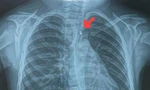

| Tình trạng phát ban hình bản đồ trên da của người bệnh mắc não mô cầu (ảnh minh họa) |